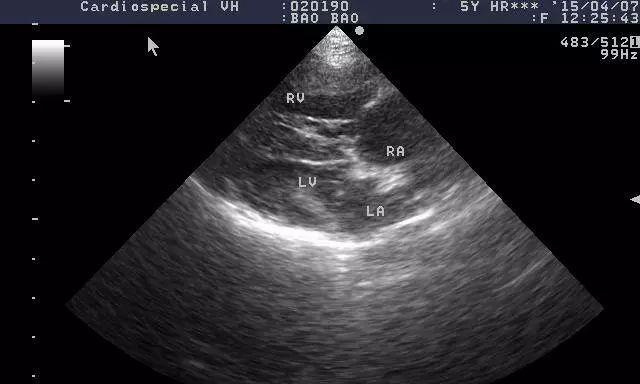

7.诊断与治疗:早期发现与有效干预

探讨以犬得心丝虫病的诊断方法和治疗手段,并强调早期发现和干预的重要性。